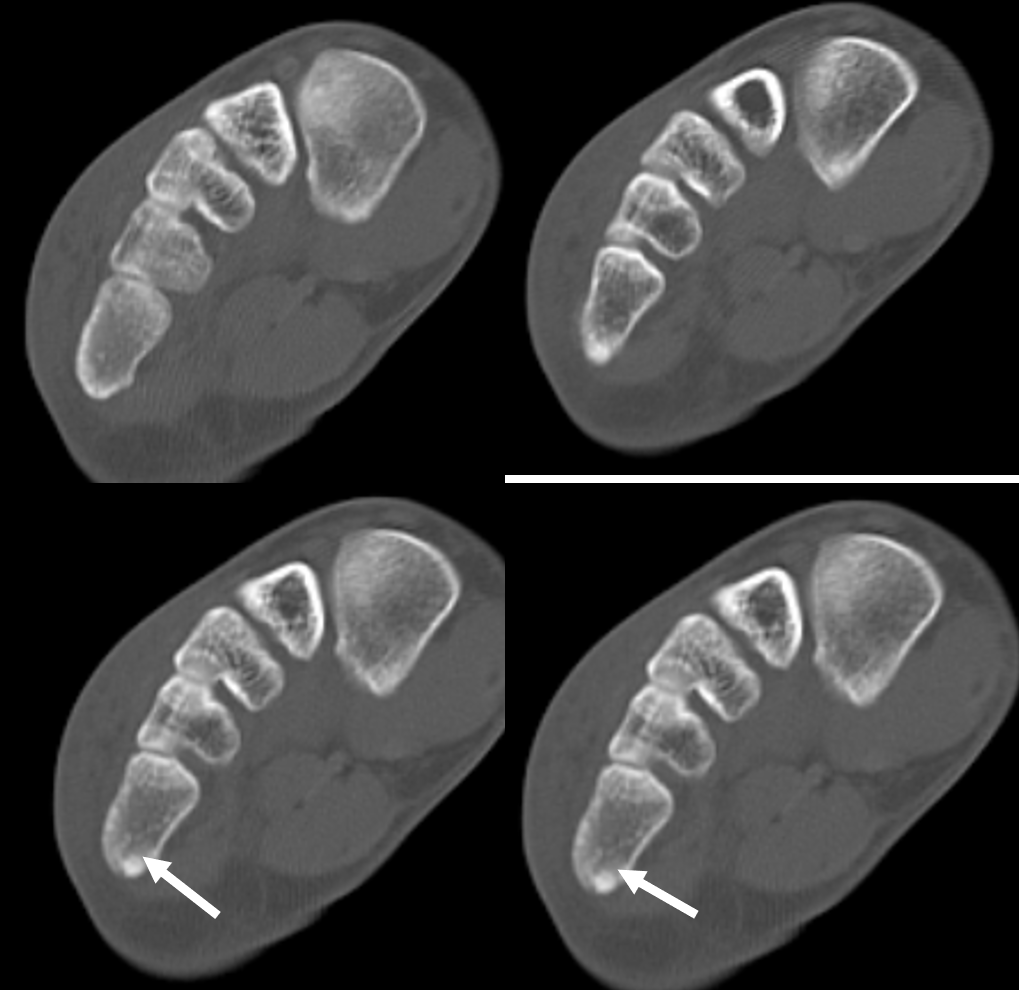

A foot radiograph revealed a suspicious radiolucency at the base of the 5th metatarsal (zone I). CT demonstrated a subtle fracture line on axial slices (indicated by white arrows). On reformatted sagittal and coronal planes, the non-displaced fracture line was clearly visible (white arrows), consistent with a pseudo-Jones fracture. Because the fracture can appear equivocal on plain radiographs and axial CT slices, long-axis reconstructions are essential for accurate evaluation in trauma patients.

For optimal fracture assessment, extremity CT scans should always be reviewed in all three planes.

Pseudo-Jones fractures typically appear as a transverse or oblique radiolucent line at the base of the 5th metatarsal tuberosity (zone I, purple), often associated with cortical step-off or minimal displacement. On plain radiographs, they may be subtle and can be obscured by overlapping structures, leading to underdiagnosis. CT, particularly with multiplanar reformations, improves detection by delineating the fracture line and ruling out intra-articular extension. MRI is not routinely required but can demonstrate associated marrow edema when the fracture is radiographically occult. Importantly, differentiation from true Jones fractures, which occur at the metaphyseal–diaphyseal junction (zone II, yellow), and stress fractures, typically arising in the proximal diaphysis (zone III, blue), is crucial, as treatment strategies and healing potential vary significantly between these entities.